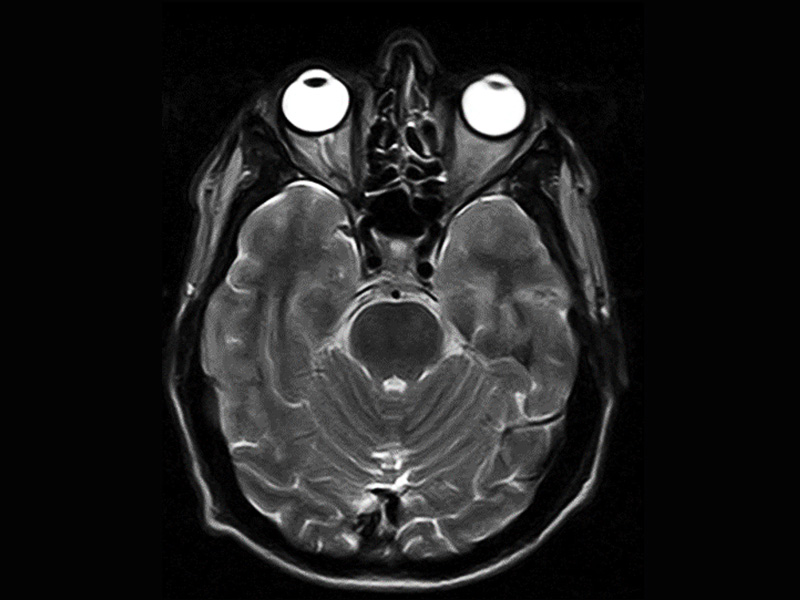

Magnifico je ten správný systém pro klaustrofobické pacienty. Otevřený magnet z něj jednoduše dělá pohodlný zážitek z magnetické rezonance pro všechny pacienty, zejména děti. Magnifico navíc přichází s průhlednou hlavovou cívkou pro větší pohodlí pacienta.

Klinické snímky